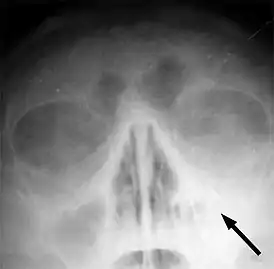

![]() Рентгеновский снимок пазух больного гайморитом (стрелкой обозначено затемнение в области верхнечелюстной пазухи, указывающее на присутствие в ней жидкости) | |